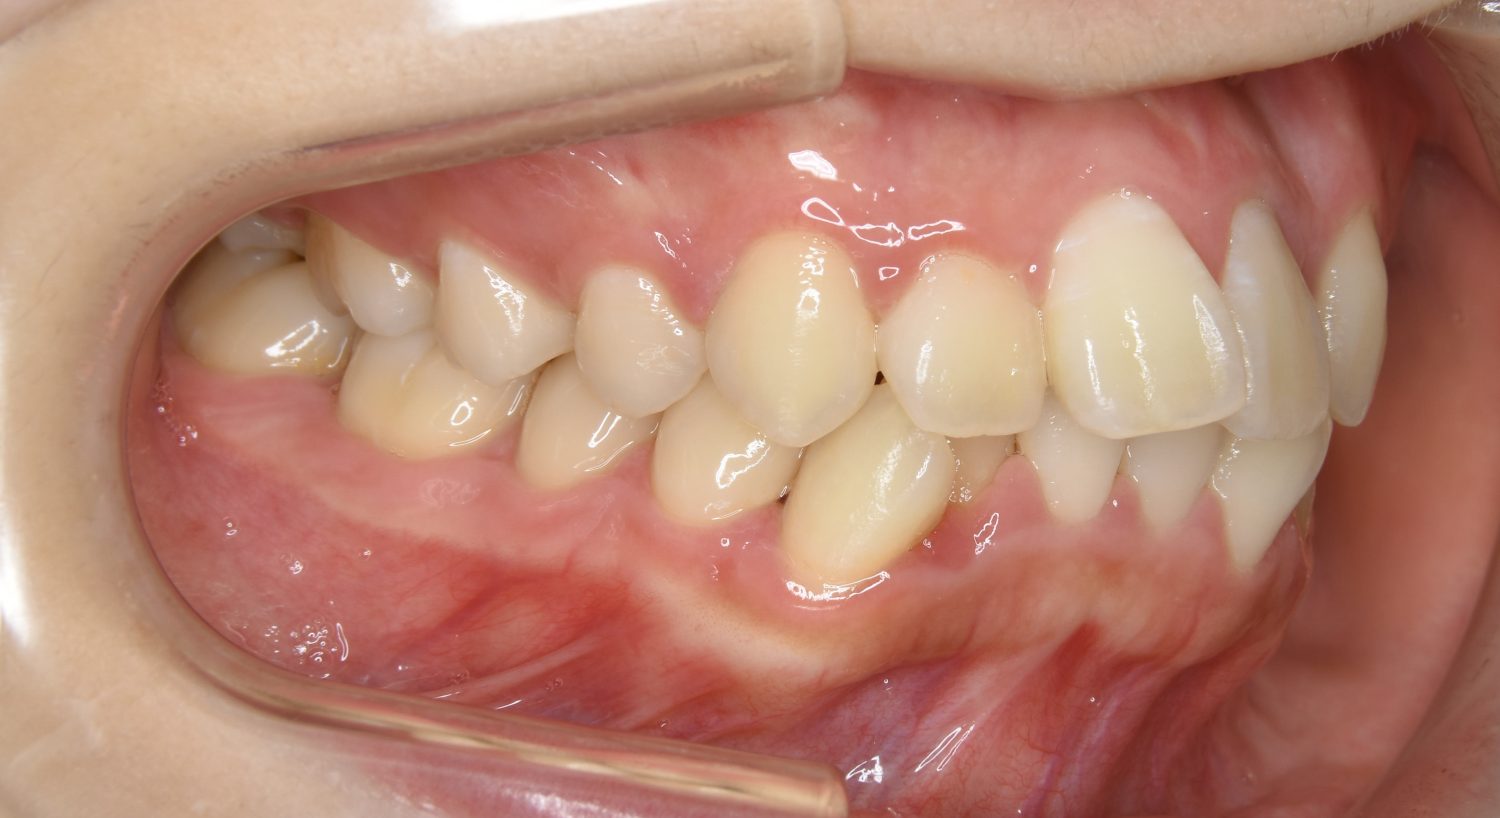

叢生の症例紹介②

Before

After

主訴

歯の凸凹を治したい。

治療内容

アライナー(インビザライン)にて非抜歯で治療を行いました。

上下前歯部に叢生(凸凹)が認められる状態でした。歯列の遠心移動を行うことで機能面および審美面が改善されました。